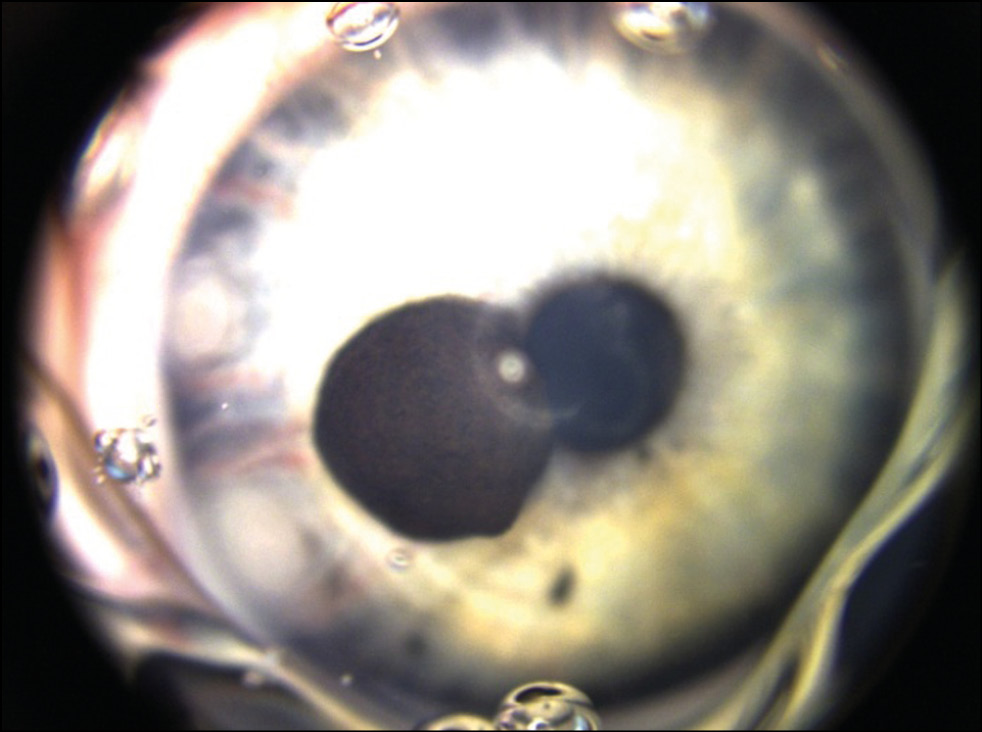

Пациентка Х., 4 года. Впервые заметили пигментное новообразование на радужке в 1 год на плановом осмотре по месту жительства. За последние 7 месяцев мама отметила рост новообразования, поэтому обратилась в Центр. Острота зрения составила 1,0. По результатам ультразвуковой биомикроскопии правого глаза отмечено в наружном отделе образование радужки размером 2,4×2,8×3,2 мм. Обследовано было затруднено в связи с маленьким возрастом ребёнка. Ребёнок был госпитализирован и обследован под общим наркозом. В результате комплексного обследования (ультразвукового исследования и Ret Cam) с учётом клинической картины было диагностировано пигментное новообразование радужки в области зрачкового края с выраженными приводящими сосудами. Отмечалось распыление пигмента по всей радужке и УПК в наружных и нижних отделах (рис. 7).

Рис. 7. Меланоцитома радужки.

По данным оптической когерентной томографии правого глаза отмечена гиперрефлективная поверхность образования с эффектом «тени» подлежащих структур (рис. 8).

Рис. 8. Оптическая когерентная томография радужки OD. Гиперрефлективная поверхность образования.

Проведена операция иридэктомия с иридопластикой правого глаза. Гистологическая картина соответствовала диагнозу меланоцитомы радужки. Пациентке рекомендовано динамическое наблюдение.